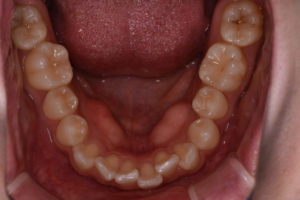

骨隆起とは、骨が何らかの刺激により、通常よりも発育しコブのように盛り上がってしまったものを指します。口の中にできる骨隆起は主に下顎隆起とよばれ、下顎の内側に形成されます。骨の隆起により、歯肉が薄くなっており、骨の隆起が歯肉を通して見えるので、白くなっていることが多いです。口の中の変化なのでなかなか確認することが難しいと思いますが、鏡で見ることができます。実際は足のくるぶしのような形態をしています。骨隆起自体には痛みや、炎症症状はありません。

骨隆起は腫瘍(癌)等とは違い硬いのが特徴です。隆起した部分の中が骨なので硬く波動はふれません(波動とは、内容物が液体の場合触ることでコブの形が変化すること)。骨隆起は、徐々に大きくなります。自然と縮小していくことはありません。炎症を伴う病態ではないので、接触による疼痛はありませんが、隆起部分の粘膜は薄くなっているので食べ物などが強くあたると痛みを感じることはあります。